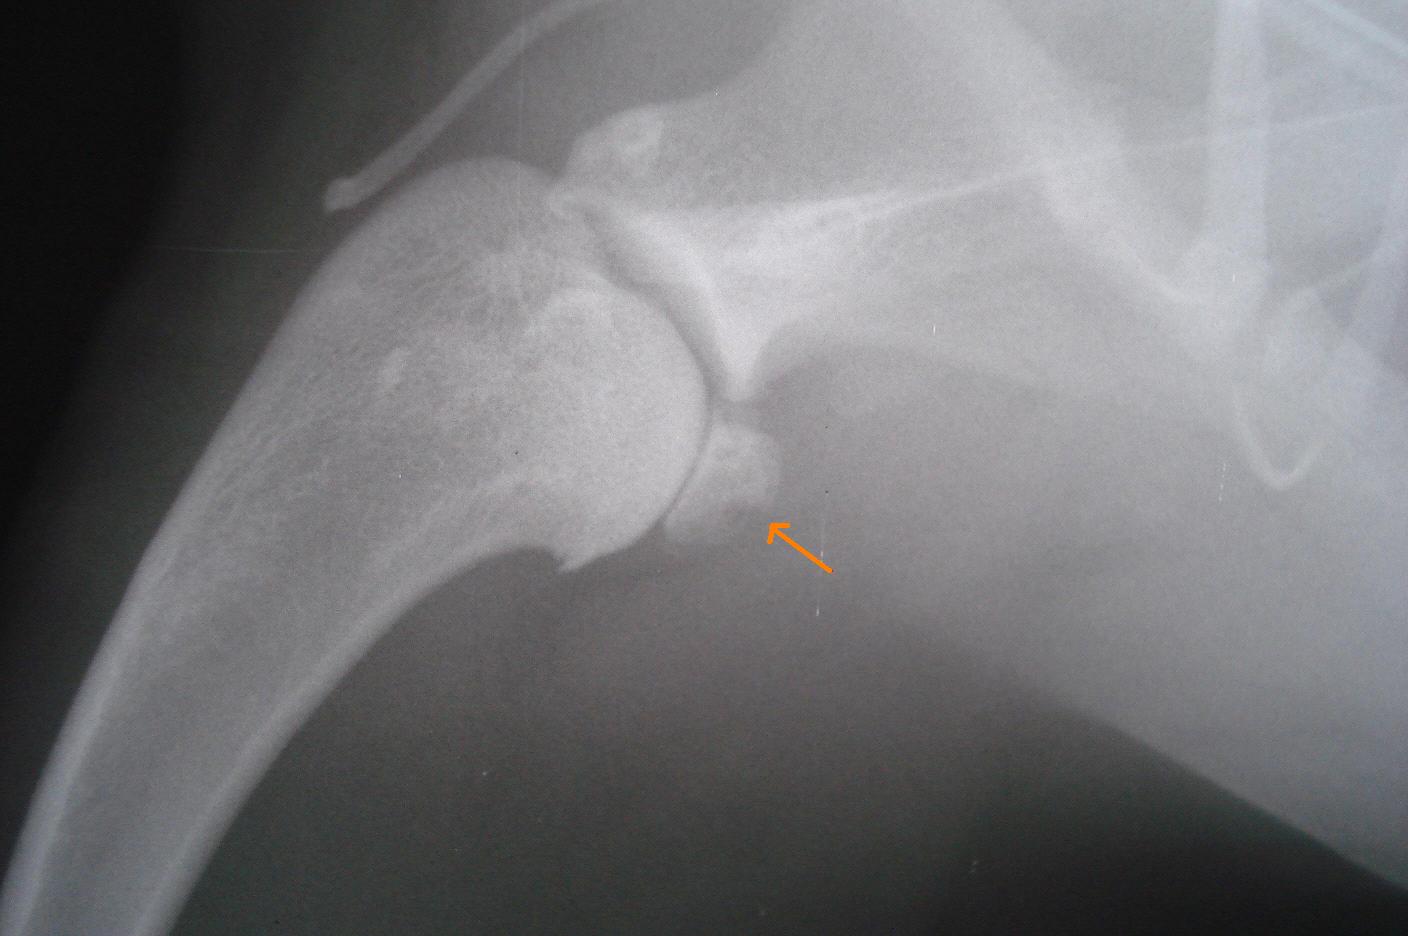

La première étape est comme souvent de consulter un vétérinaire le plus rapidement possible. Il pourra, à l'aide de manipulations articulaires ou de radiographies, estimer les dégâts provoqués par la maladie et proposer des solutions adaptées à chaque cas.